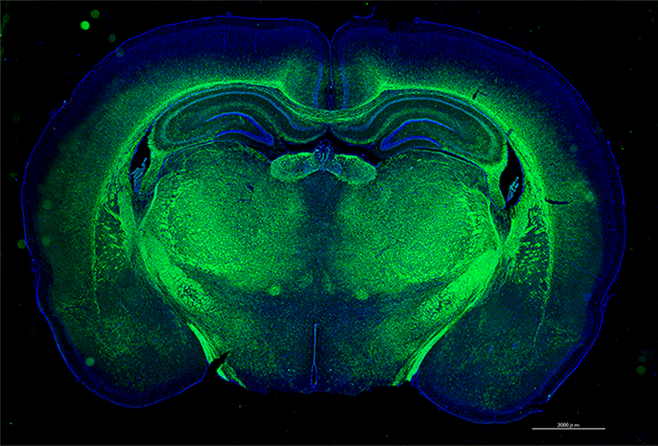

研究内容

遺伝的に病気を発症する動物(遺伝的疾患モデル動物)を用いて、ヒトや動物の病気の原因や発症メカニズム、治療法の研究を行っています。